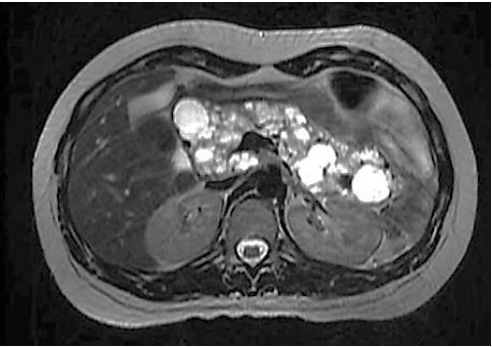

Paciente realiza ressonância magnética que individualiza múltiplas formações císticas pancreáticas, conforme a imagem a seguir:

Fonte: Arquivos Brasileiros de Endocrinologia e Metabologia, v. 43, n. 5, out. 1999.